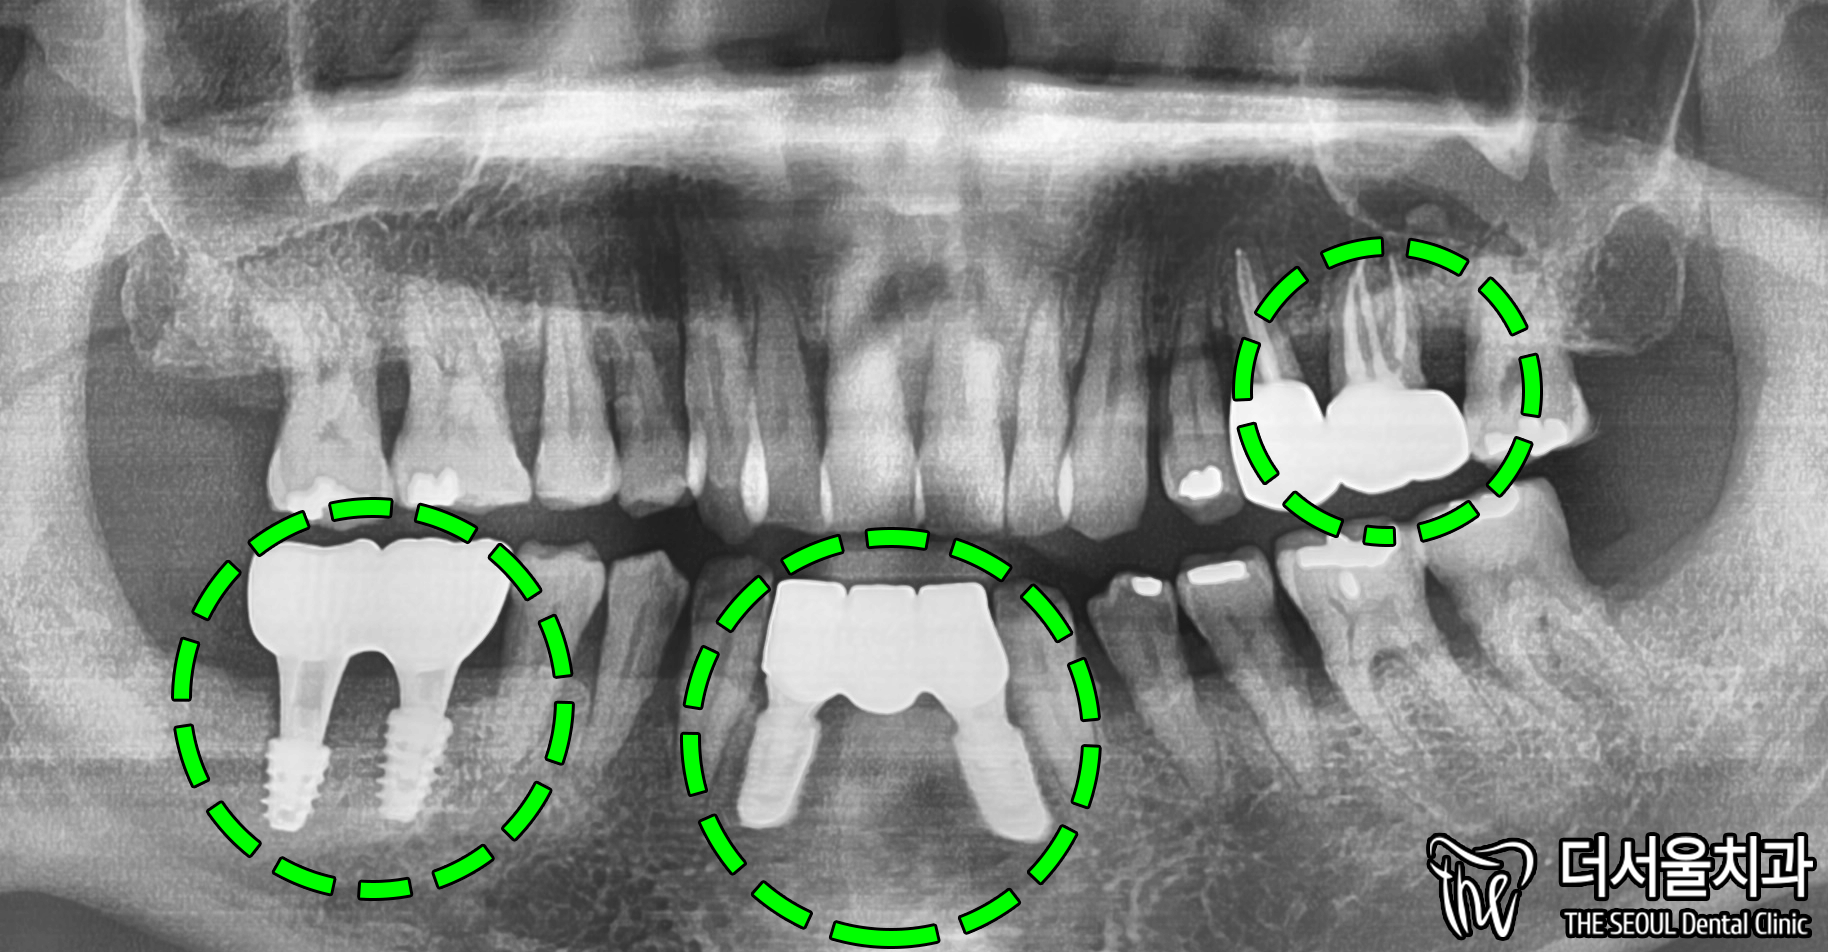

먼저 내부는 어떠한지

좀 더 정확한 진단이 필요했기에

엑스레이를 찍어봤습니다.

우측 아래 어금니 부분을 보면,

염증 너무 커서 뼈 소실까지

심하게 일어나 있었습니다.

이정도로 커진 케이스는

무조건 뼈이식을 진행할 수밖에 없습니다.

또, 전반적으로 남아있는 잇몸뼈를 보면,

고르지 않고 울퉁불퉁 합니다.

특히 아래 부분이 심각합니다.

엑스레이로 한번 더 체크하여

식립한 임플란트가 잘 심어졌고,

신경치료한 어금니도

말끔하게 처리된 모습을 볼 수 있습니다.